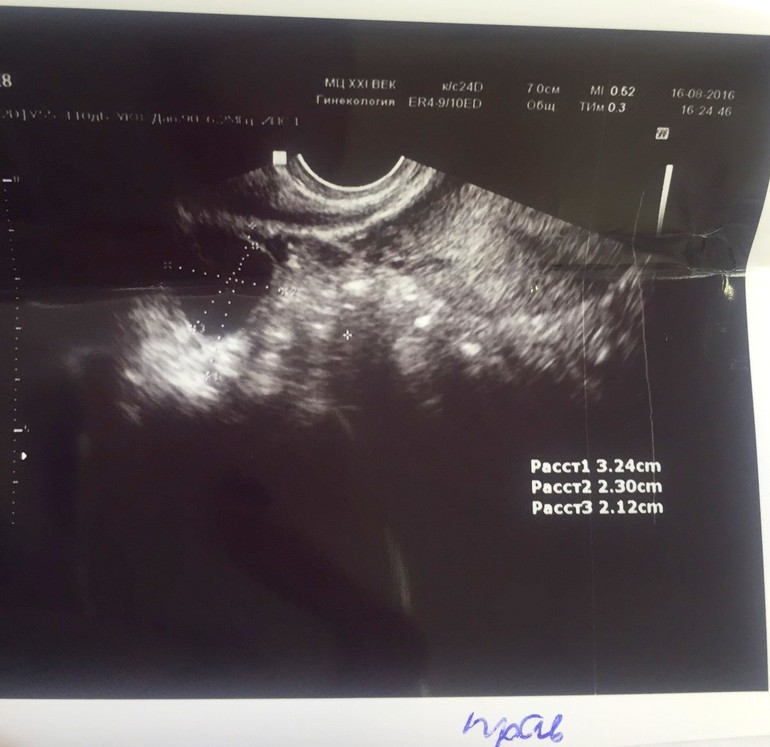

Вчера была у своей Г., пошла по ДМС сдавать анализы (беспокоили боли как при М внизу живота) думала даже что М. придут рано в связи с тем что по узи на 12 и 16 ДЦ не было ДФ.

Взяла анализы, и говорит давай узи сделаем, а там в каждом яичнике по ДФ 21, и 20 мм я в шоке, вот тебе и на, а ведь уже 23 дц. Удивительно, надеюсь не сдуются, эндик 7 мм думаю что подрастет еще. Никогда не было так поздно овуляции (четко всегда 14-16 дц)

картинка ниже